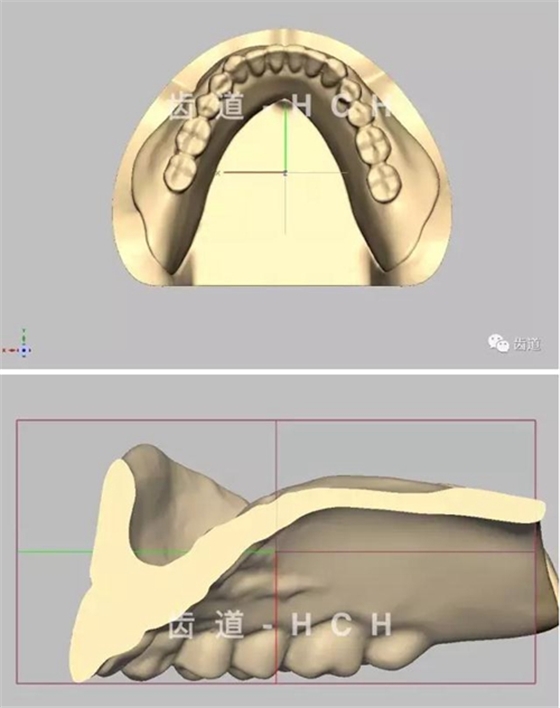

標(biāo)準(zhǔn)全口義齒模型截圖 科貿(mào)嘉友收錄